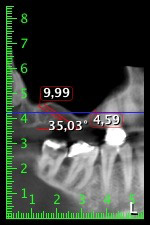

La paciente de 59 años presentaba una periodontitis avanzada, describía una desagradable sensación y un mal gusto proveniente del primer cuadrante. La evaluación clínica mostró en general marcadas profundidades de bolsa y una degeneración ósea muy avanzada en las regiones 16 y 14. El estudio radiológico corroboró estos resultados (figura 1). Las piezas dentales 16 y 14 no podían conservarse.